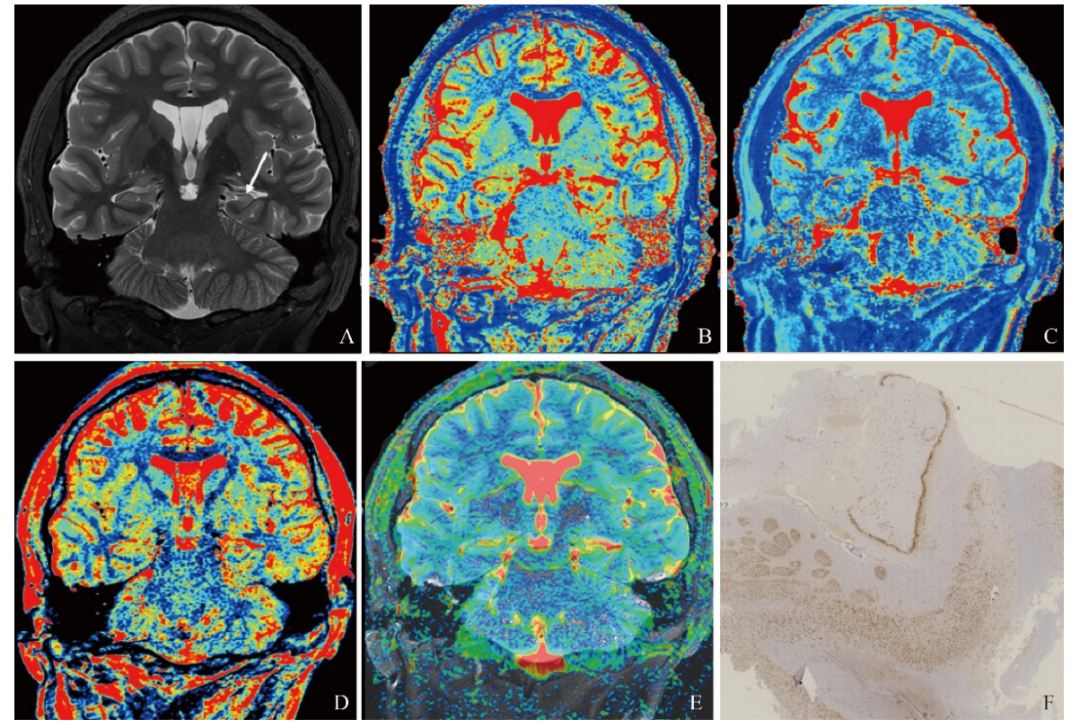

MTLE-HS患侧与对照组及健侧海马T1、T2、ADC值比较,差异均有统计学意义(P均<0.05),PD差异无统计学意义(P>0.05),患侧海马T1、T2、ADC值明显高于健侧及对照组(P均<0.001)(表1)。典型MTLE-HS病例见图1。

图1  男,18岁,癫痫病史15年,手术病理证实为左侧HS,A~F分别为斜冠状位T2WI、T1 mapping、T2 mapping、PD mapping、ADC、海马病理切片图,患侧(左)T1、T2、PD、ADC值分别为1 743 ms、115 ms、84 pu、1087×10-6 mm2/s;健侧(右)值分别为1466 ms、89 ms、85 pu、899×10-6 mm2/s